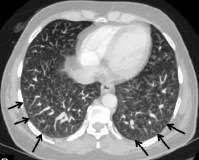

• Ангиопульмонография. При тяжелой гипоксемии рентгеноконтрастное изображение артериовенозных шунтов в легких выполняется как подготовка к инвазивному лечению. Во время исследования врач изучает состояние сосудистой сети, оценивает размер крупных легочных артерий и мелких периферических сосудов.